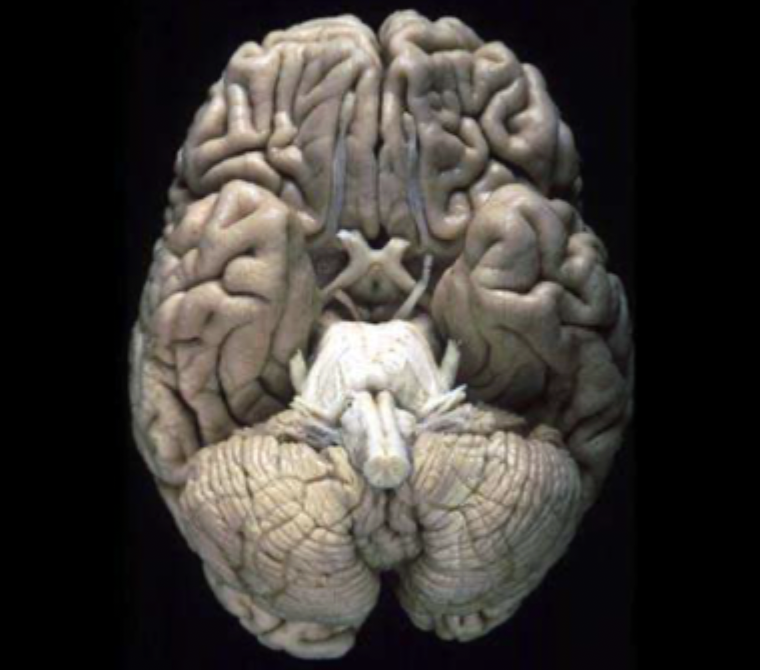

What view of the brain is this?

the ventral/inferior view